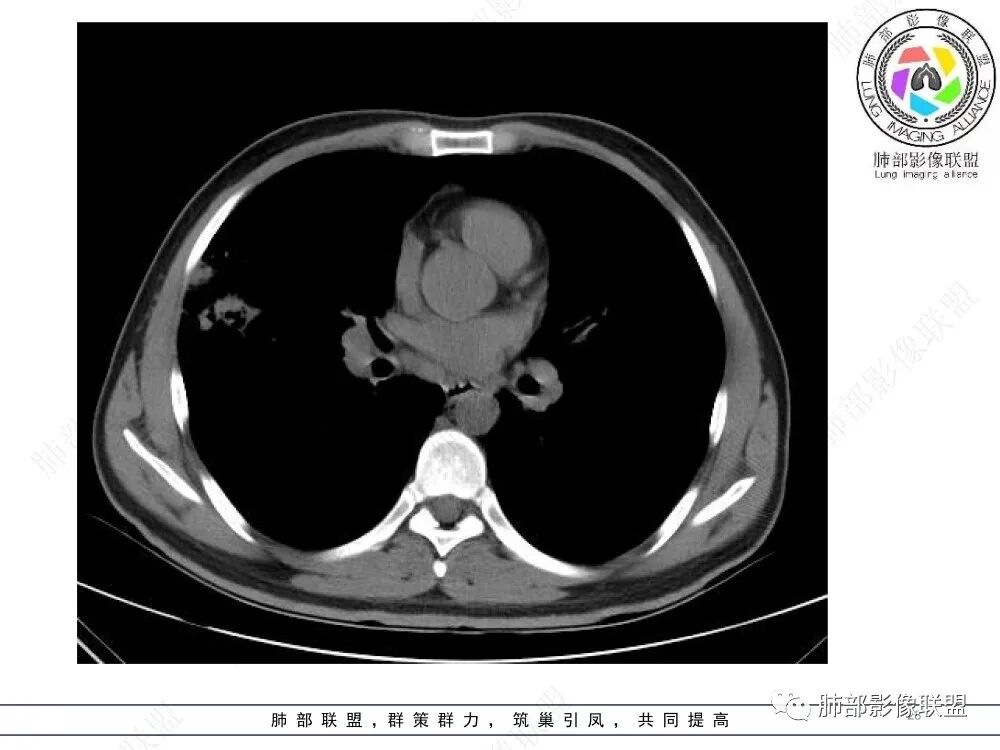

中年男性,慢性咳嗽,有吸烟史,胸部CT基础尚可,双肺多发的沿支气管播散的树芽影以及支气管管壁的增厚和对应区域内的斑片影实变影,符合气道播散的表现。经过对症抗感染治疗1月之后,胸部CT影像进展。右侧播散到左侧。实变和漱牙以及气管壁增厚均较前明显进展。

2.胸部CT:两肺广泛的支扩,支气管壁增厚,多发的树芽影,部分伴有支气管周围的渗出,少量实变。不足一月复查,原有支扩、支气管壁增厚基础上伴有大量渗出,实变,结节,胸膜下累及。

3.综合分析:首先病灶沿支气管分布,呈树芽征及实变影,相应支气管壁广泛增厚,其次病变范围比较广泛,几乎累及所有叶段,这种表现常高度提示气道播散,经过对症抗感染治疗20多天后,胸部CT影像明显进展。符合IPA的进展表现。